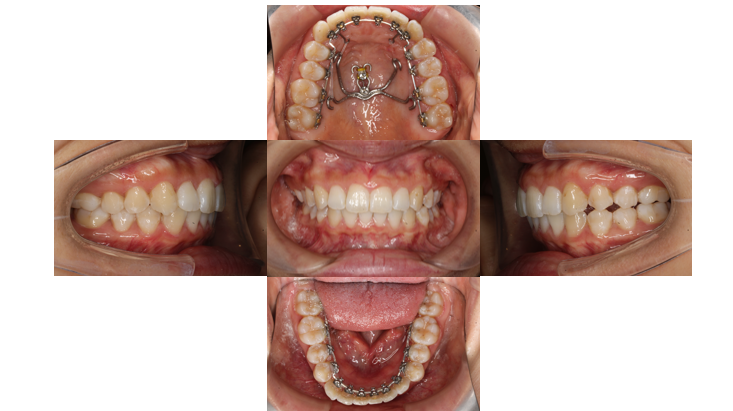

かみ合わせを治したい(通院期間:1年4か月/通院17回)

Before

After

主訴 | 【主訴】かみ合わせが深い【診断・症状】過蓋咬合 |

抜歯 | 無(非抜歯) |

矯正の装置 | リンガル矯正 |

上下裏側に装置がつきました

下の歯と装置が当たる場所があるので青い材料を歯に盛り、当たらないようにしています

噛み合わせを良くするためにボタンを使用し、ゴムかけをしていきます

歯と装置が当たらないようになったので青い材料を外します

右側から3番目の歯は他の歯と比べてねじれがある歯なのでゴムかけをして改善していきます

上あごのフックで最後の微調整をしていきます